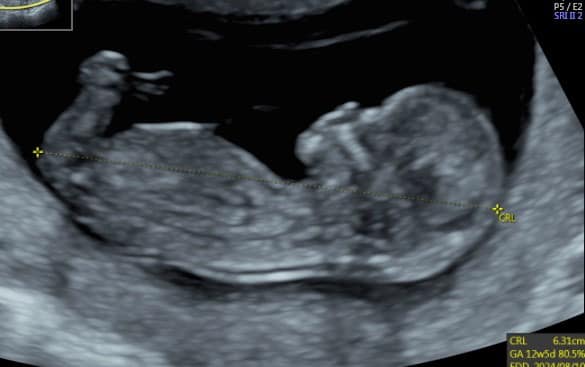

A Szülni Jó Központban az első trimeszteri ultrahang során kiterjesztett vizsgálat történik, melynek alatt hozzávetőleg 50 struktúrát nézünk át egy 12-13 hetes magzatnál az anyai kismedencei képletekkel együtt.

Az első trimeszteri ultrahang szűrést betöltött 11. héttől 13 hét 6 napos terhességi korig javasolt elvégezni, ez az intervallum az ideje a kombinált tesztnek is. Ebben az időszakban 45 mm és 83 mm közötti nagyságú magzatokat vizsgálunk. Hogy érzékeltsebb legyen: egy szokásos névjegykárta 90mm hosszú. Az egyik célja a vizsgálatnak, hogy a vizsgált képletek alapján már több magzati anatómiai fejlődési rendellenességet kizárjunk. Ezek még a nagyon durva, általában élettel nem összeegyeztethető, vagy az életminőséget jelentősen befolyásoló rendellenességek körébe tartoznak.

CRL(ülőmagasság): Az ülőmagasság mérése szinte az alapja a vizsgálatnak, mert minden egyéb marker ehhez a mérethez van viszonyítva.